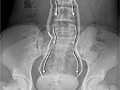

An intravenous pyelogram (IVP) is an X-ray test that provides pictures of the kidneys, the bladder, the ureters, and the urethra (urinary tract). An IVP can show the size, shape, and position of the urinary tract, and it can evaluate the collecting system inside the kidneys.

During IVP, a dye called contrast material is injected into a vein in your arm. A series of X-ray pictures is then taken at timed intervals.

The injection site on your arm will be cleaned and the contrast material will be injected into a vein on the inside of your elbow. The dye travels through the bloodstream, is filtered out by the kidneys, and passes into the urine. The urine then flows into the tubes (ureters) that lead to the bladder.

X-ray pictures are taken several minutes apart as the dye goes through the urinary tract. Each picture is developed right away. Sometimes more pictures are taken based on earlier ones. You may be asked to turn from side to side or to hold several different positions so the radiologist can take a complete series of X-rays.

During IVP, a compression device may wrapped around your belly to keep the dye in the kidneys. The most common compression device is a wide belt containing two inflated balloons that push in on either side of your belly to block the passage of dye through the ureters. If you have recently had abdominal surgery or have an abdominal disorder, the band will not be used.

An intravenous pyelogram (IVP) is an X-ray test that provides pictures of the kidneys, the bladder, the ureters, and the urethra (urinary tract). Your doctor may be able to talk to you about some results right away. Complete results are usually ready in 1 to 2 days.

Intravenous pyelogram (IVP)

Normal:

The kidneys, ureters, and bladder are normal in position, size, and shape.

The contrast material reaches the kidneys in a normal amount of time.

No blockage can be seen in the kidneys, ureters, or bladder.

In men, the prostate gland looks normal in position, size, and shape.

Abnormal:

The kidneys, ureters, or bladder may be abnormal in position, size, or shape. A kidney may be absent, or an extra kidney or ureter may be present.

The kidneys are too large or too small.

The contrast material takes longer than normal to reach a kidney.

An abnormal growth (such as a tumor), one or more cysts, an abscess, or a kidney stone is seen.

A kidney is swollen with urine from a blockage such as a tumor or kidney stone.

Injury to the kidney, ureter, or bladder is seen.

The kidney contains scarring.

In men, the prostate gland is too large.